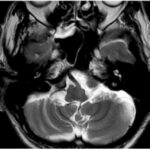

La lesión se localiza en el puente dorsomedial, en una topografía correspondiente al colículo facial, región formada por el núcleo del nervio abducens y las fibras intrapontinas del nervio facial que lo rodean. Este territorio se asocia clásicamente con el síndrome del colículo facial, caracterizado por la afectación de los circuitos oculomotores horizontales y del nervio facial.(5, 11, 12)

Desde el punto de vista anatómico, el compromiso del núcleo del VI par y de la formación reticular paramediana puede explicar la alteración de la mirada horizontal ipsilateral, mientras que la afectación de las fibras del nervio facial justifica la parálisis facial periférica ipsilateral. La ausencia de una extensión ventral significativa hacia la base del puente favorece este diagnóstico frente a otros síndromes pontinos mediales, como el síndrome de Foville, que típicamente asocia compromiso del tracto corticoespinal.(11, 12)